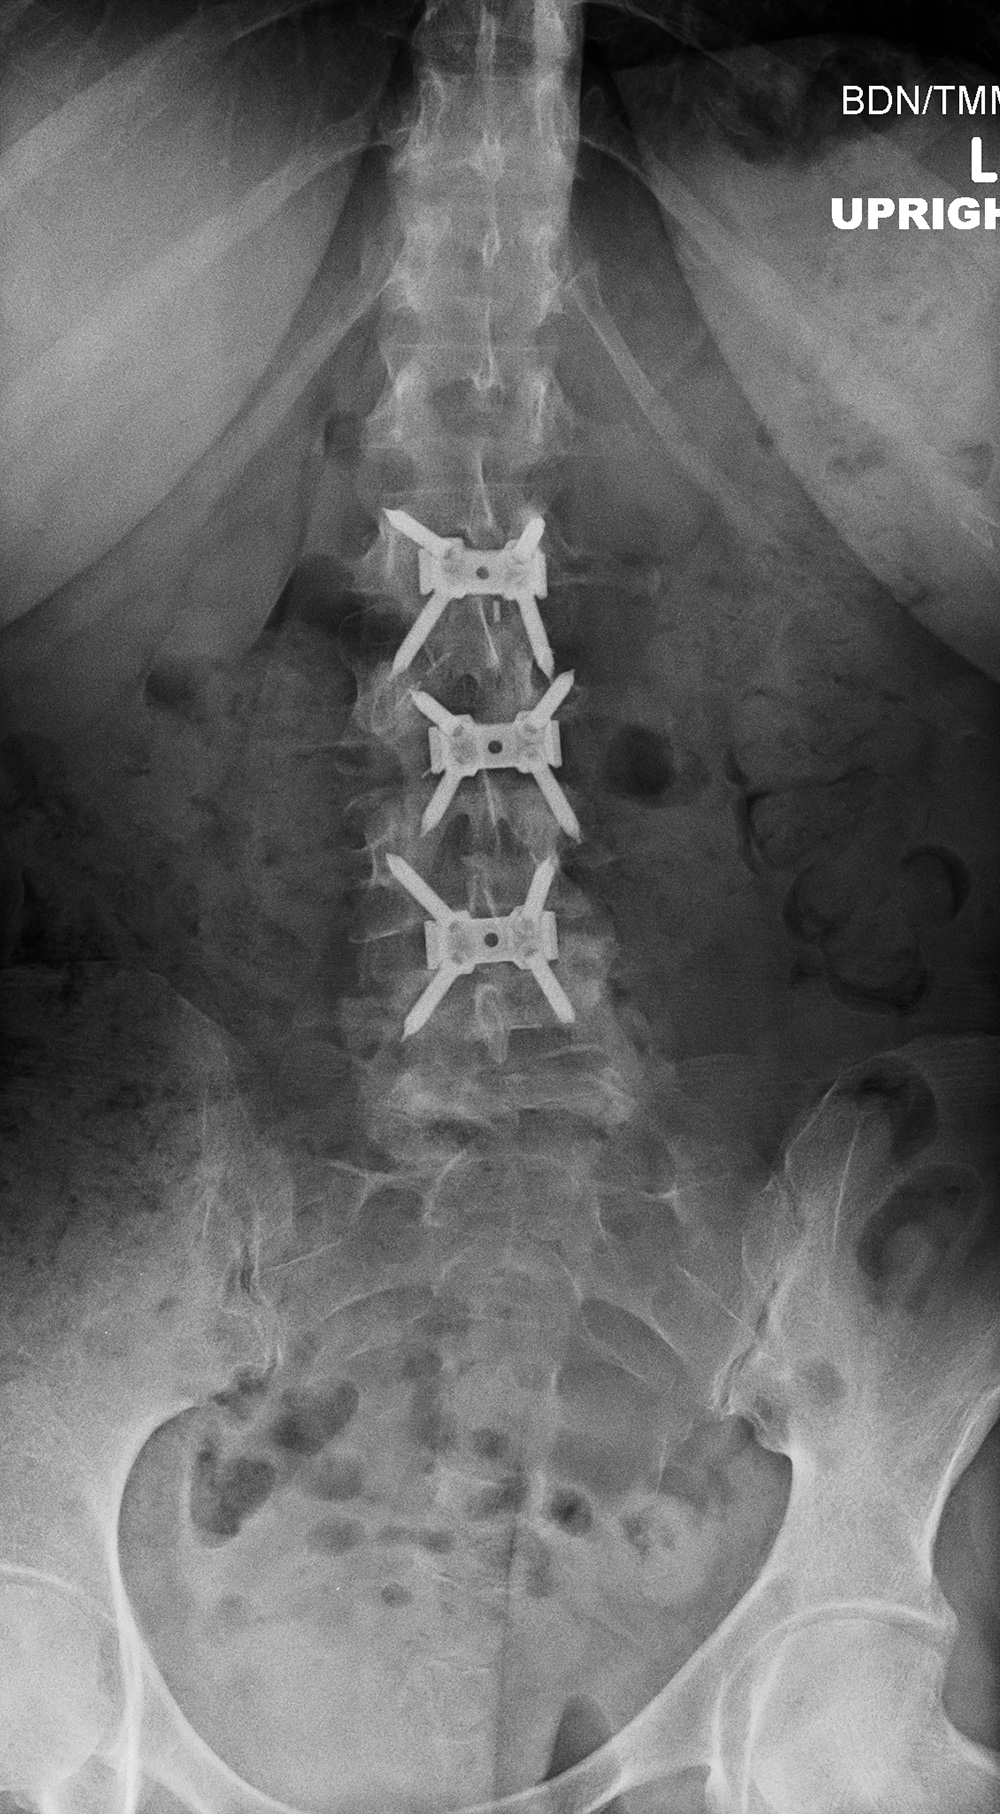

Anterior lumbar interbody fusion (ALIF) has become more popular and is a somewhat limited procedure (figure: ALIF; figure: zero-profile lumbar fixation L2-5). It offers an easy approach to the anterior disk space without opening the spinal canal or neural foramina, such as the case with posterior lumbar interbody fusion (PLIF) or transforaminal lumbar interbody fusion (TLIF). ALIF allows the placement of a large interbody fusion device and easy and complete diskectomy (Mobbs, 2013). ALIF is used for chronic back pain of discogenic origin over 1 - 3 levels.

ALIF is often performed with zero-profile systems using a low profile spacer anchored by fixation screws into vertebral bodies above and below the diskectomy level (figure: zero-profile lumbar fixation L2-5). The native disks are usually replaced with PEEK artificial disks. While ALIF is somewhat of a more limited surgery compared to several other approaches, it has the disadvantage of potential vascular or bowel injury resulting from the anterior approach to the spine. There has to be mobilization of the great blood vessels and peritoneal contents away from the spine exposing them to possible injury (Mobbs, 2013).

| Zero-Profile lumbar fixation L2-L5 |

| 45 year-old woman with L2-5 anterior lumbar interbody fusion (ALIF) for low back pain. The lateral views are respectively in neutral and flexion positions. The CT images are selected slices in the coronal and sagittal planes, respectively. |

| Zero-Profile lumbar fixation L2-L4 |

| 45 year-old woman with L2-5 anterior lumbar interbody fusion (ALIF) for low back pain. |